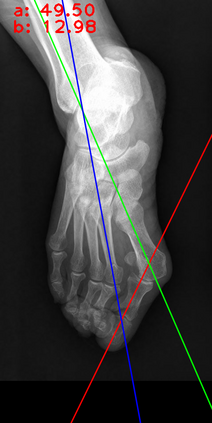

Angular measurements is essential to make a resonable treatment for Hallux valgus (HV), a common forefoot deformity. However, it still depends on manual labeling and measurement, which is time-consuming and sometimes unreliable. Automating this process is a thing of concern. However, it lack of dataset and the keypoints based method which made a great success in pose estimation is not suitable for this field.To solve the problems, we made a dataset and developed an algorithm based on deep learning and linear regression. It shows great fitting ability to the ground truth.